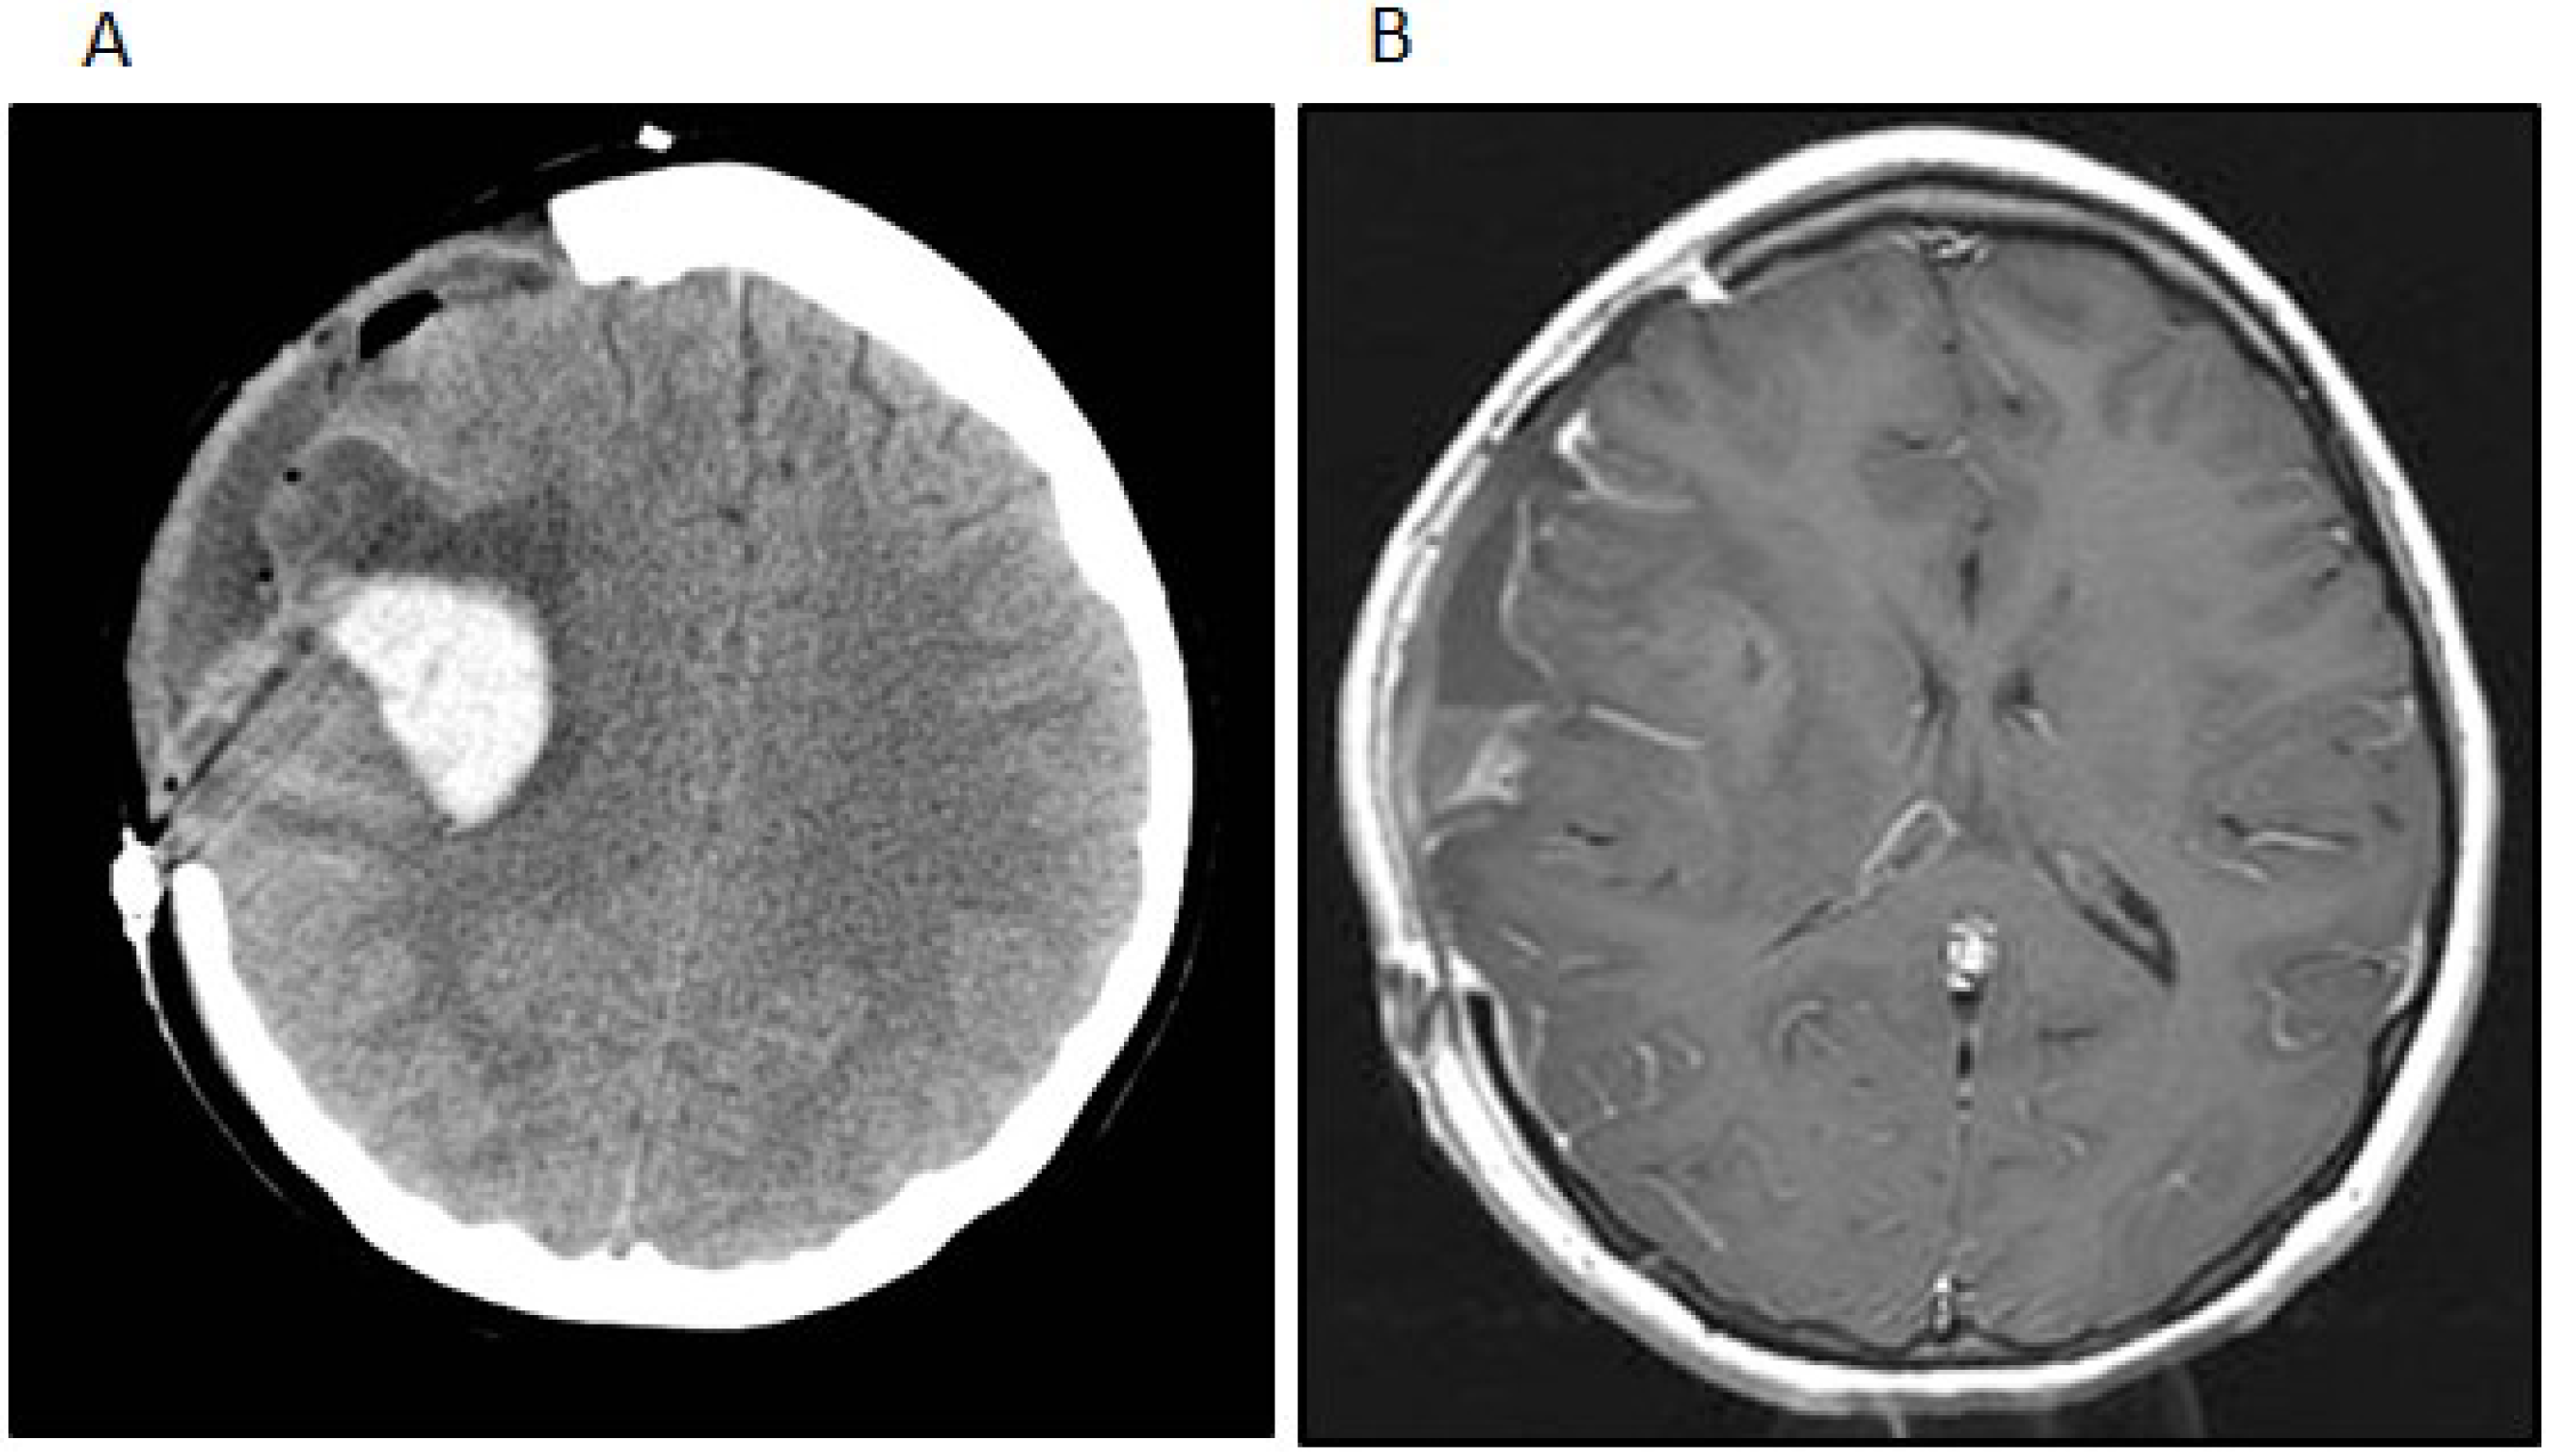

Postoperatively, the patient remained neurologically intact. One month after her initial surgery, however, the patient developed a rapidly worsening mental status that progressed to coma. Imaging studies showed a hemorrhage within and an interval growth of the tumor (Figure 3A). The patient underwent an emergent craniotomy with the evacuation of the hemorrhage and near total resection of the residual tumor (Figure 3B). Although the patient experienced a complete recovery from a cognitive standpoint, she did have a severe left-sided hemiparesis. Two months after the emergent surgery, she underwent another craniotomy for the resection of the recurrent tumor and replacement of her bone flap in preparation for radiation therapy. At that time the tumor was noted to be densely adherent to the overlying dura and temporalis muscle, from which all gross tumor was removed. The resected tumor revealed a few minute areas of infiltration into superficial cortex with no bulk tumor identified within the brain. However, areas of dural infiltration and some infiltration of the temporalis muscle were identified.

Figure 3. (A) The patient developed a delayed intratumoral hemorrhage requiring hemicraniectomy and evacuation of the hemorrhage and tumor. The noncontrast head CT shows the acute hemorrhage within the right Sylvian fissure extending into the right frontal lobe; (B) The post-contrast t1-weighted image after the second surgery shows subtotal removal of the neoplasm and evacuation of the intratumoral hemorrhage.